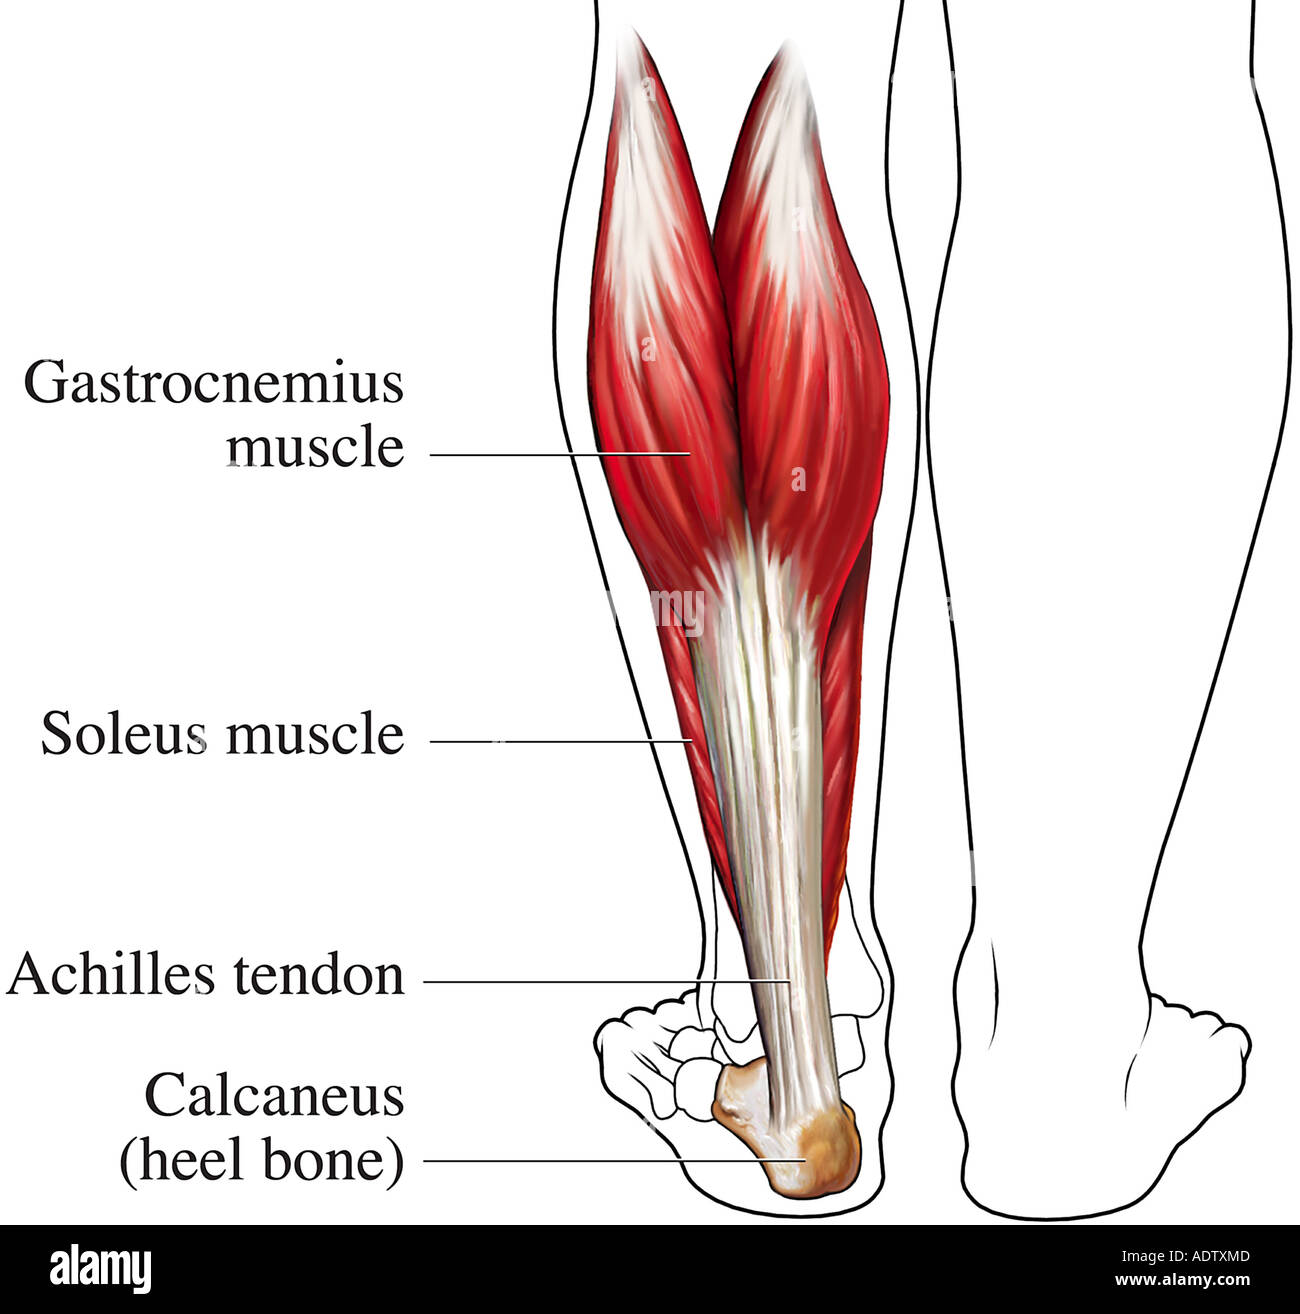

Musculare hi-res stock photography and images – Alamy